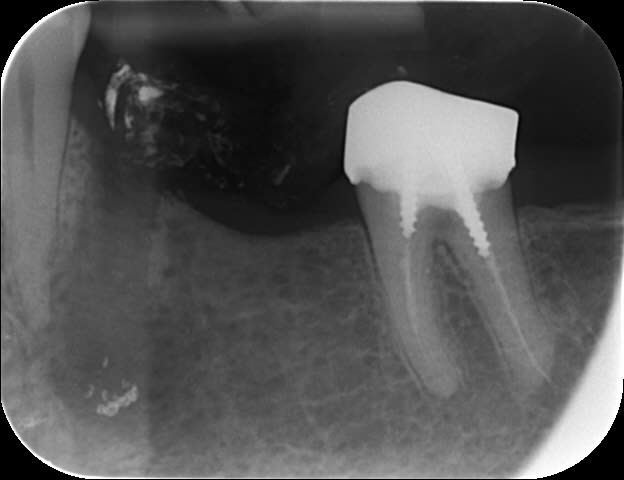

Patient vu à l'instant pour infection traitée il y a 3 semaines sur 35 et joyeux dépassement maintenant douloureux.

Mais j'ai eu un remord : si on curette juste la zone apicale causale, cela doit valoir la peine de tenter la réimplantation.

Moi je l'ai fait. Patiente que j'avais adressé à deux chir pour résection apicale pour une 46, ils ont refusé. Mobilité 3. Beau foyer apical. RTE du tiers apical impossible.

Je me suis souvenu des regles de réimplantation: extraction rapide avec luxation verticale. J'ai prevenu la patiente sur les probabilité de réussite.

Je l'ai extraite, fait la résection apicale dans la main, réimplantée, même pas de contention. Je vous raconte pas les yeux de l'assistante que je n'avais pas prévenu...

Un an après, pas d’ankylose, guérison totale du foyer apical.